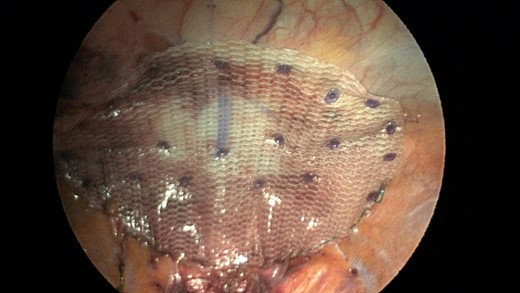

A sleeve of Parietex composite mesh cut to act as a suture bolster under the diaphragm edge to prevent the sutures from pulling through the diaphragm muscle.

CT scan is obtained for a specific diagnoses of Morgagni hernia in order to strategize your surgical approach. Minimally invasive laparoscopic techniques have become a popular option in the 21st century due to reduced intraoperative morbidity and quicker recovery rates [9]. Our case was unique in that the novel use of a sleeve of composite mesh was used as a bolster for the Ethibond suture as opposed to felt pledgets so the suture would not pull through the diaphragm. This sleeve of mesh was separate from the main mesh that was used to cover the overall repair (see pictures).